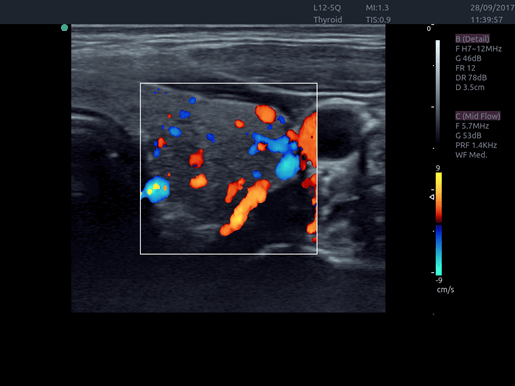

Invictus E5

O ultrassom Invictus E5 apresenta um design moderno e exclusivo, com perfeito fluxo de trabalho e interface intuitiva.

Dentre suas características inovadoras, podemos destacar a tela em LCD com rotação de 60° para ambos os lados, para otimização da visualização durante os exames; tela touch screen com menu totalmente customizável; painel de controle totalmente selado para facilitar limpeza e desinfecção da superfície, o que o torna referência para ser utilizado principalmente em Centro Cirúrgico.

Apresenta excelente qualidade de imagem, trabalho otimizado através de presets pré-determinados, sensibilidade e eficiência em aplicações de Point of Care e portanto, uma perfeita relação custo benefício.